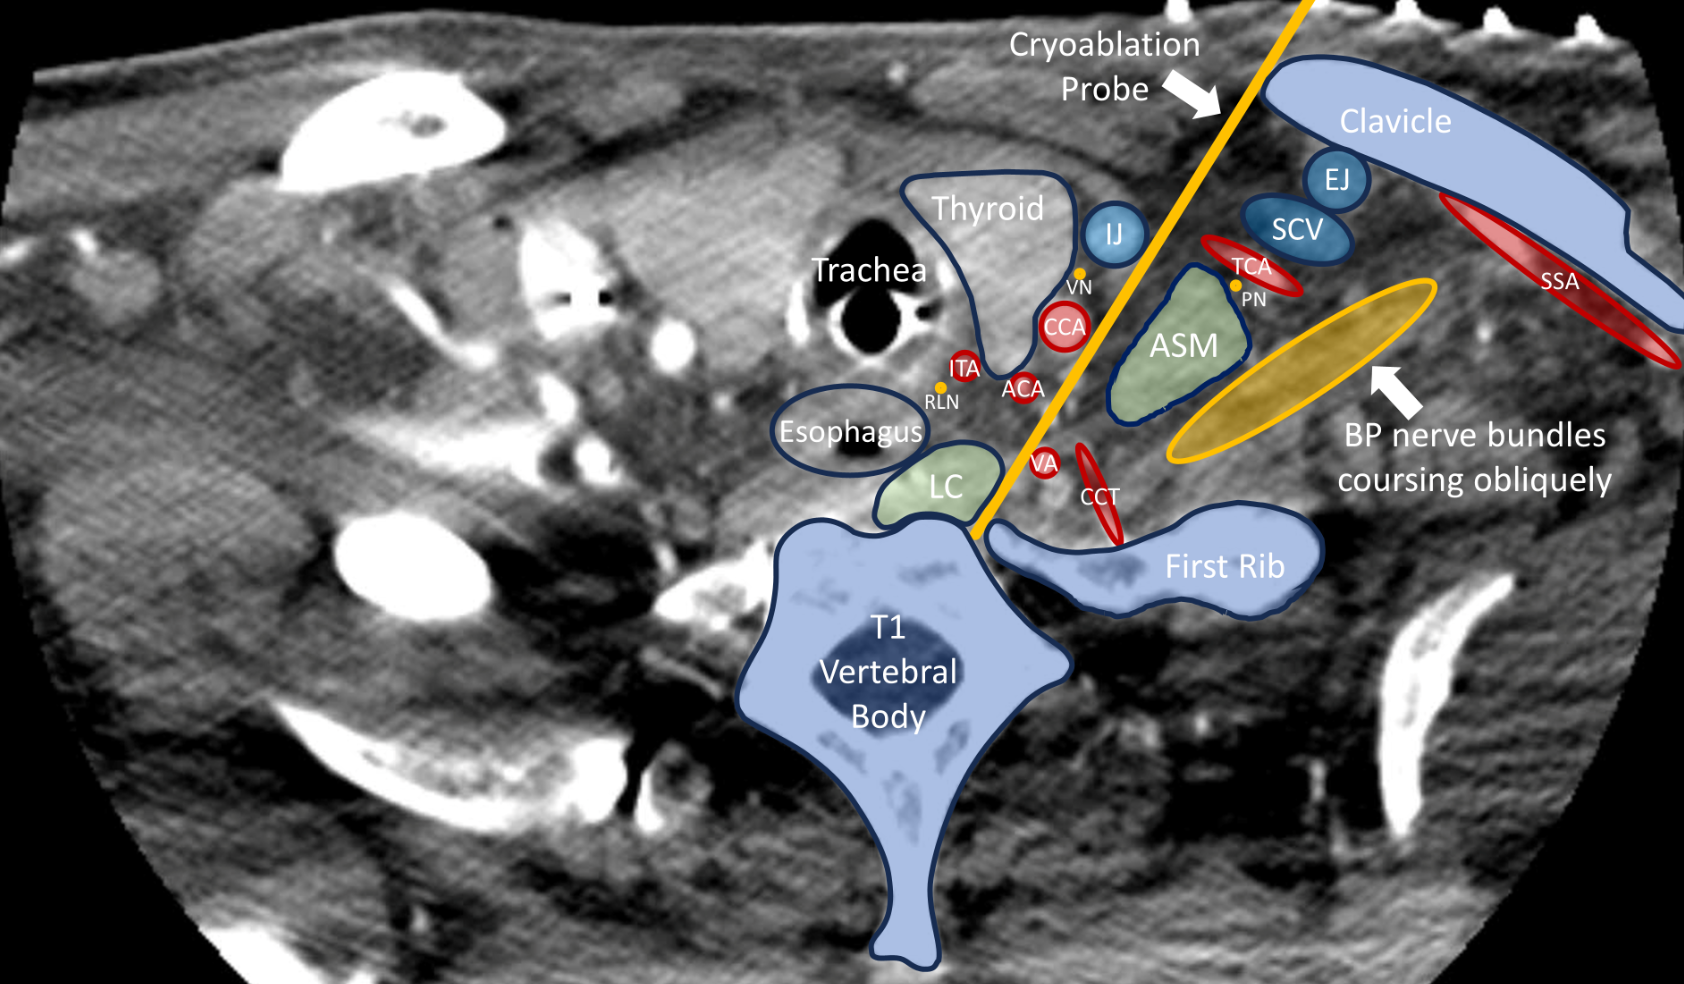

We use cryoneurolysis techniques to manage complex pain and autonomic disorders. Key areas include stellate ganglion ablation for refractory ventricular arrhythmias and PTSD, along with celiac plexus/splanchnic nerve cryoneurolysis for abdominal pain in chronic pancreatitis and pancreatic cancer, complemented by other targeted nerve interventions.

- Reference: Li, N., Kim, J., Patel, A.M., Markham, D.W., Tompkins, C.M., Rahban, Y., Stokken, G., Gottbrecht, M., Prologo, F.J. and Resnick, N.J., 2024. CT-guided Left Stellate Ganglion Cryoneurolysis for Refractory Ventricular Arrhythmias. Radiology, 313(3), p.e240587. https://doi.org/10.1148/radiol.240587